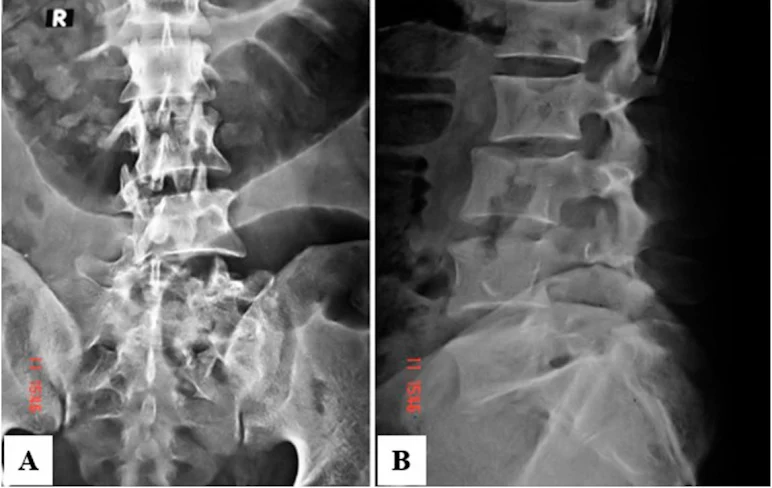

Una mujer de 49 años se lesionó el ligamento cruzado anterior (LCA) cuando era estudiante de secundaria. La reconstrucción del LCA de haz doble (DBACLR) con injertos de tendón de la corva se realizó debido a la inestabilidad recurrente. Once años después de la DBACLR, se realizó una artroplastia total de rodilla debido a la progresión de la osteoartritis. Se completó el análisis histológico para observar la osteointegración del tendón en la tibia proximal obtenida. El túnel tibial mostró fibras similares a Sharpey en la parte anterior, conectando el injerto de tendón y el hueso laminar, mientras que la salida intraarticular reveló condrocitos bien alineados en la parte posterior, lo que indica una metaplasia condral del injerto de tendón.

La curación del tendón-hueso puede regenerar tanto la inserción fibrosa como la metaplasia condral en DBACLR.